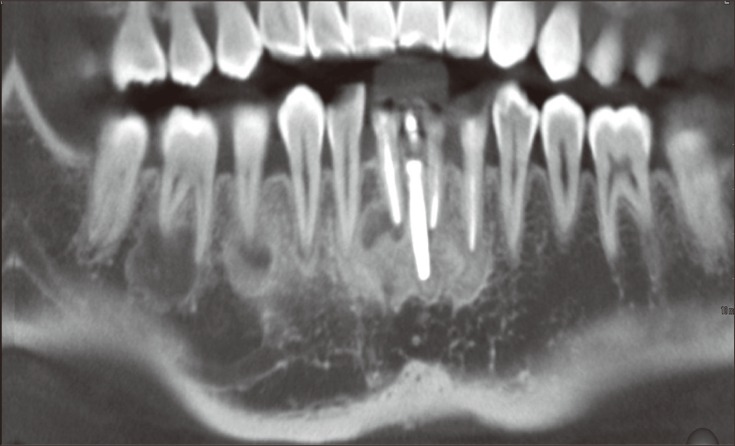

In the periapical areas of #32, 33, 36, 42, 43, 45, 46 and the implant, lobular-shaped radiolucencies that contained small radiopaque masses were revealed by computed tomography (CT, Somatom Sensation 64, Siemens, Munich, Germany, 120 Kvp, 90 mA). All of the lesions were related to the cortical plates, and perforation of labial and lingual cortical bones was observed on the mandibular lateral incisors. No cortical bony expansion was detected (Figure 3). Periapicies of maxillary teeth were examined as normal condition.

Figure 3

Computed tomography (CT) images at the initial visit. (a) A panoramic reconstruction of the CT images at the level of the apices. Multiple lesions bony lesions were detected; (b) Axial images of #42, 32, and 46 at the apical level. Mixed radiopaque and radiolucent lesions as well as cortical bone perforation were observed; (c) Vertical images showing thinning and perforation of the cortical plate without any expansion.